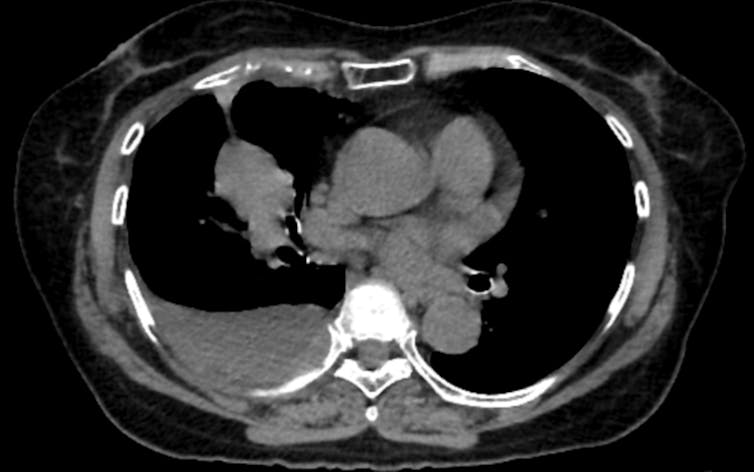

Coronary artery calcium, or CAC, is probably the best demonstration of what opportunistic screening can accomplish. When calcium builds up in the walls of the coronary arteries, it reflects underlying atherosclerosis, the disease process behind most heart attacks. CAC scoring is one of the strongest predictors of future heart attacks, and it adds predictive information beyond what traditional risk calculators provide.

Dedicated cardiac CT scans can measure this calcium precisely. So can a standard lung cancer screening CT, if someone takes the time to look. Studies have found that calcium measurements from lung screening CTs agree closely with those from dedicated cardiac scans, meaning the information is there even when the scan was not designed for cardiac evaluation.

That overlap matters because roughly 19 million noncardiac chest CTs are performed each year in the United States. Every one of those scans passes through the heart. The presence of calcium is visible in the images – yet studies find that when CAC is present, radiologists report it in fewer than half of cases.

A single cross-sectional image from a chest CT shows a mass in the patient’s right lung and fluid surrounding the lung.